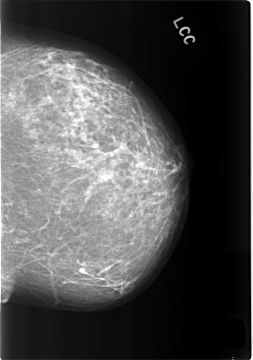

C_0286_1.LEFT_CC

LEFT_CC LINES 5760 PIXELS_PER_LINE 4040 BITS_PER_PIXEL 12 RESOLUTION 50 NON_OVERLAY